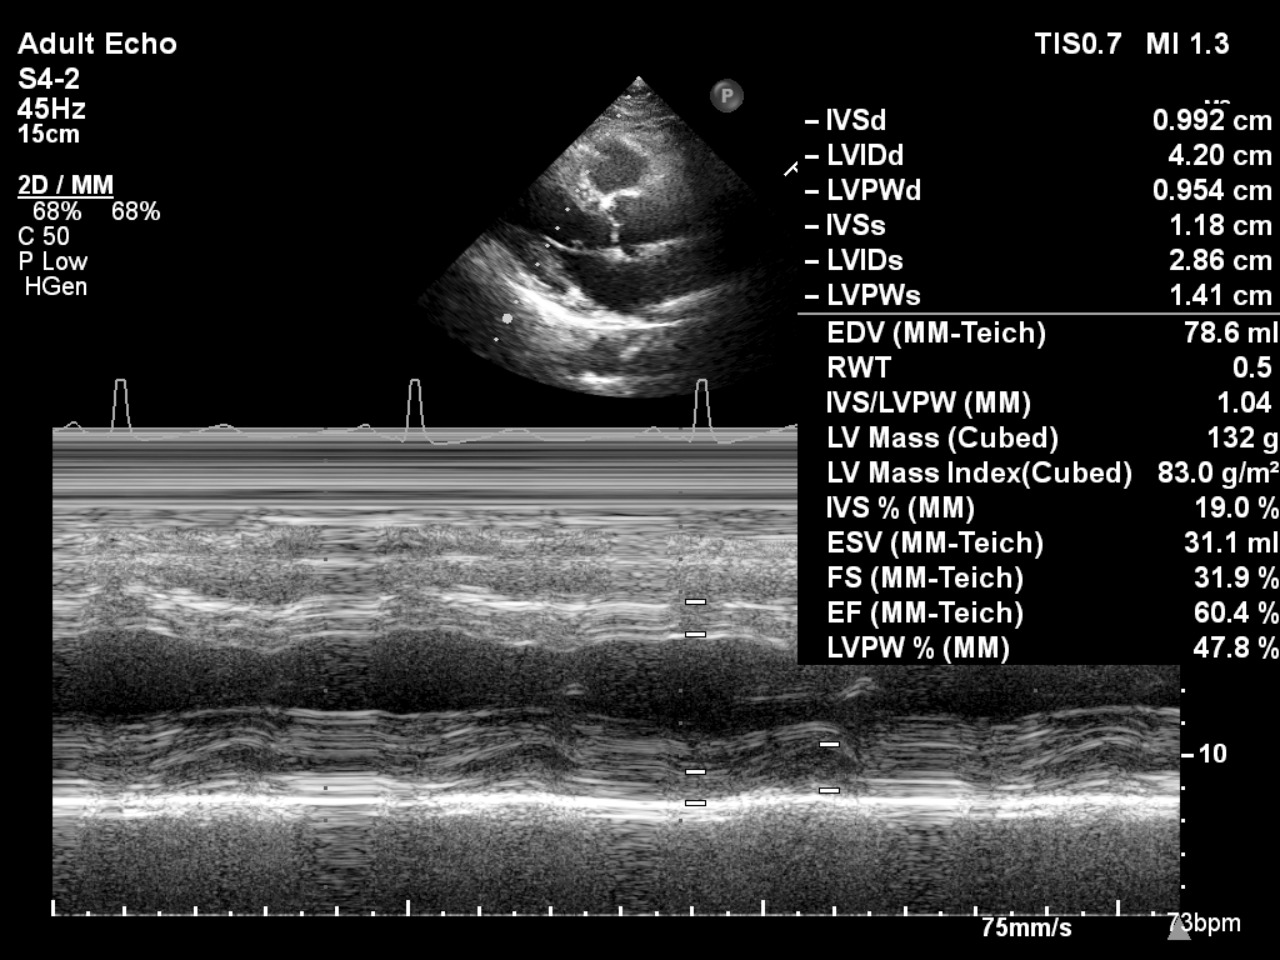

Electrocardiogram: ST elevation in aVR and V1 with widespread ST depressionEchocardiography: EF 60.4% with anteroseptal hypokinesia. No significant valvular abnormalities.